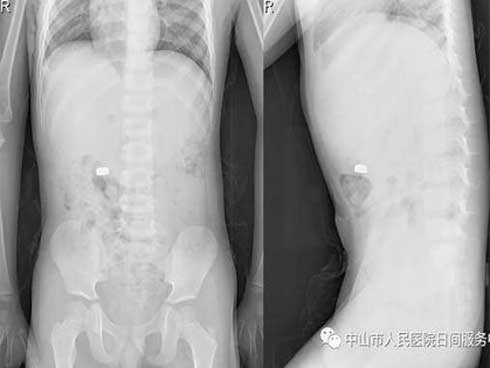

Bà Trần Kim Khánh (bà nội bé Hoa) cho biết cách đây 13 năm bé Hoa được bác sĩ chẩn đoán mắc bệnh teo mật bẩm sinh. Tuy nhiên, khi gia đình đã không phẫu thuận mà về bốc thuốc nam cho bé uống. Tới khi bé Hoa được 14 tháng tuổi bụng trướng to như quả bóng sắp vỡ gia đình mới đưa bé quay trở lại viện.